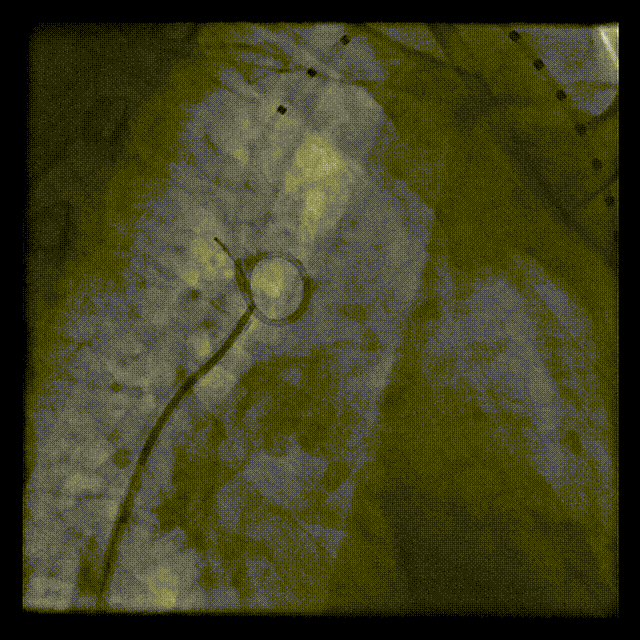

左锁骨下动脉送入圈套器抓捕Terumo软导丝,使导丝头端体外化,建立左桡动脉-弓离断-右股动脉导丝轨道,建立通路。

建立通路